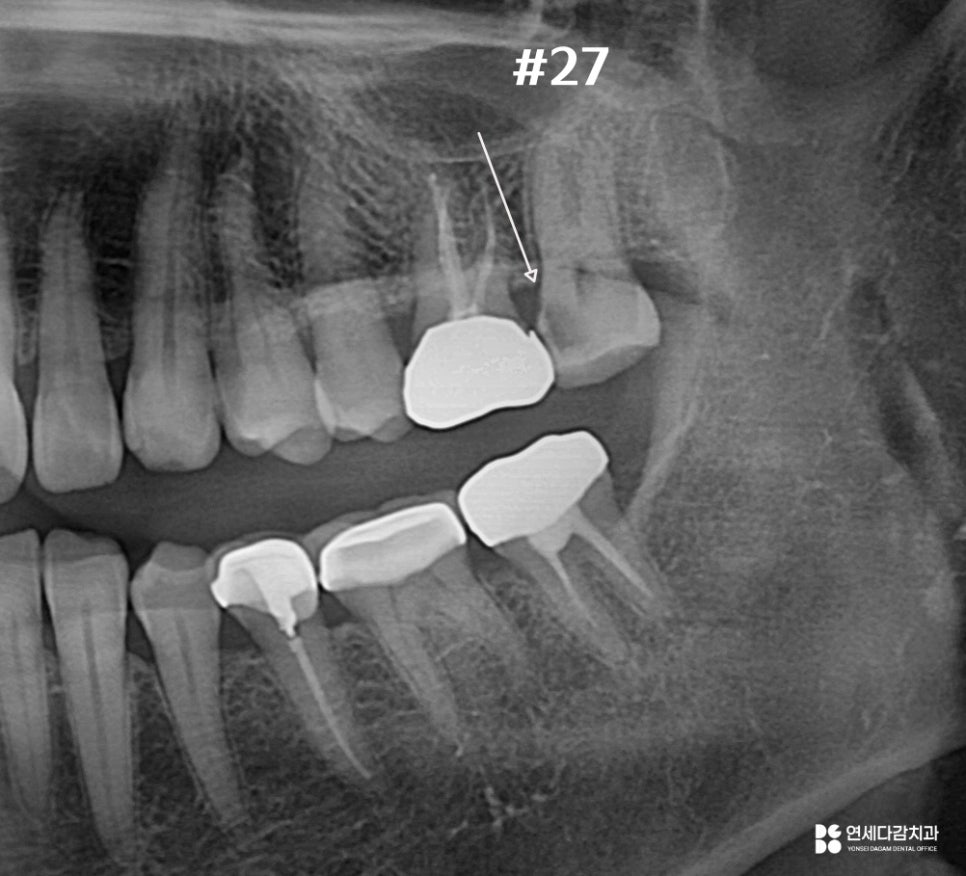

위와 같이 엑스레이에서도

병변이 명확히 확인할 수 있는 반면,

실제로 병변을 정리해 보기 전까지는

정확히 알 수 없는 부분도 존재합니다.

개롱역 치과 에서 설명해 드리는

대표적인 것이 신경 침범 여부입니다.

방사선 사진상으로

치수 근처까지 도달한 것처럼 보이더라도,

실제로 치수까지 이어졌는지는

직접 제거해 보아야 알 수 있습니다.

46번이 그런 경우입니다.

초진 사진에는 내부 깊이 확산되었지만,

다행히 침범하지 않은 상황입니다.

이런 경우 크라운 치료를 진행하고,

경과를 지켜보게 됩니다.

2025.11.12

반면 27번처럼

충치 제거 과정에서 치수 조직으로

우식이 이어진 것이 확인된다면

신경치료를 진행하게 됩니다.